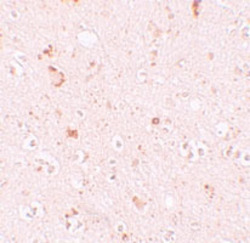

PAB19296 IHC

Immunohistochemistry